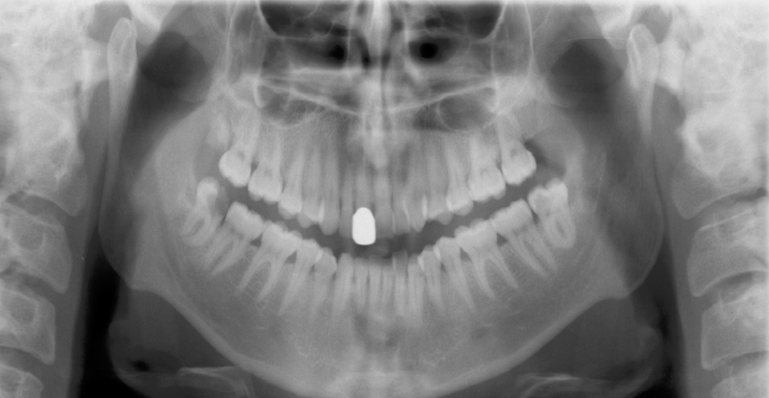

32

What is wrong with this image?

TONGUE NOT AT ROOF OF MOUTH - palatoglossal air space